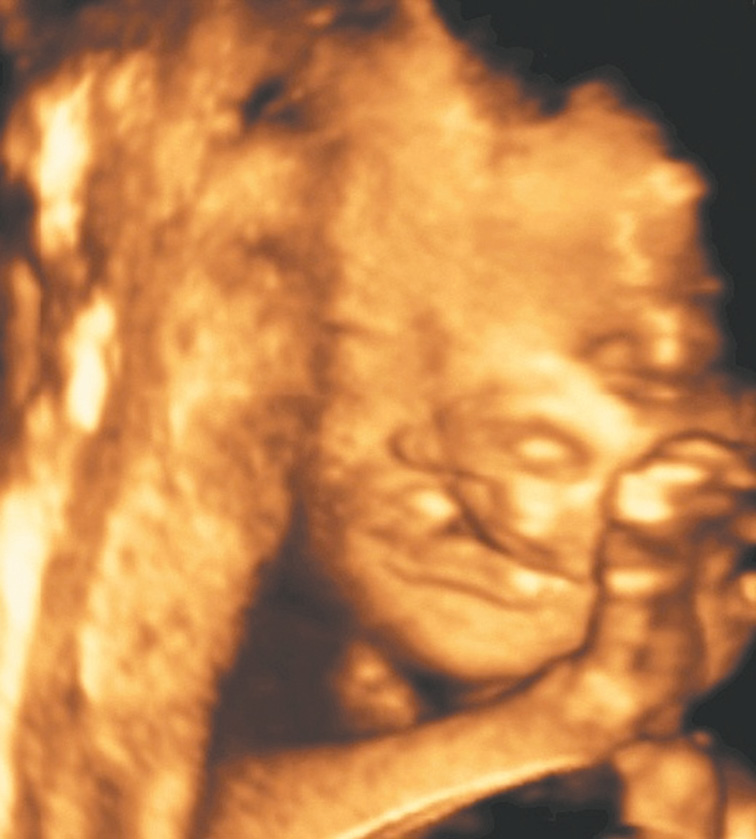

В настоящее время профилактика врожденных аномалий челюстно-лицевой области — это своевременная диагностика [2]. Применение трехмерной ультразвуковой диагностики плода беременной женщины открывает новые возможности для предотвращения серьезных челюстно-лицевых деформаций, поскольку самый важный период в формировании зубочелюстной системы — внутриутробный (рис. 2).

Рис. 2. Дефект верхнего нёба. Порок развития плода / Fig. 2. Upper palate defect. Malformation of the fetus

Цель 3D-ультразвукового исследования состоит в создании объемного изображения в отличие от двухмерного метода, создающего плоскостные сечения [6, 11]. Объемная картина получается при сканировании смежных сечений — это объем пространства пирамидальной формы (рис. 3, 4).

Рис. 3. Плод, 31 неделя, 3D-ультразвуковое исследование / Fig. 3. Fetus, 31 weeks, 3D